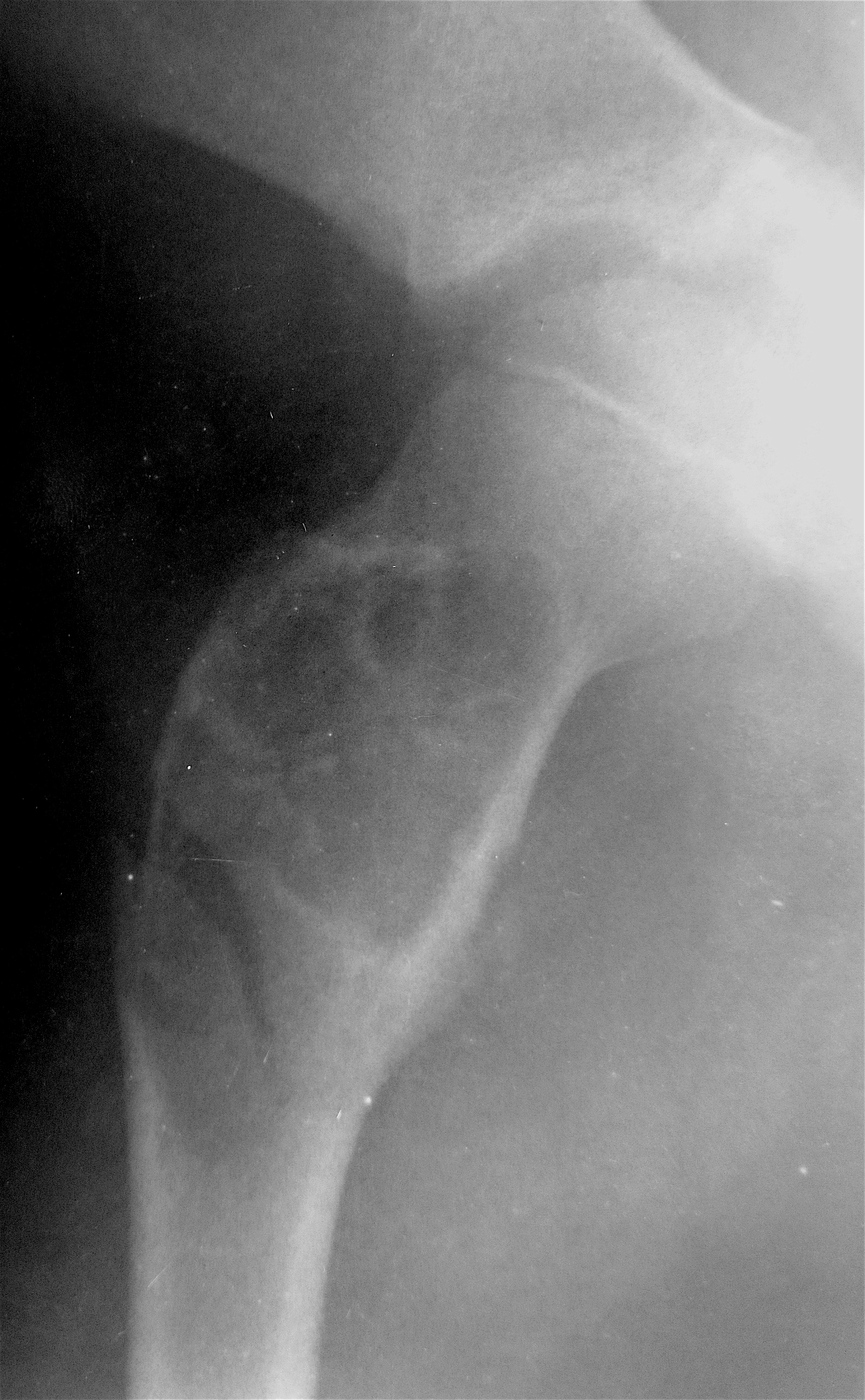

Закрытый, паталогический перелом в подвертельной области правой бедренной кости со смещением, на фоне аневризмальной костной кисты.